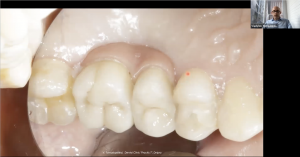

Операционный микроскоп является штатным оборудованием любого стоматологического кабинета. Работа с микроскопом позволяет хирургу стоматологу избавить своих пациентов от необоснованных страданий, а так же работать эргономично, что сохраняет здоровье доктора на долгие годы. Информация, полученная на данном вебинаре, позволит Вам лучше разобраться с необходимыми характеристиками микроскопа и знать основные понятия при работе с таким оптическим устройством. Материал вебинара предоставляет фактические рекомендации по работе хирурга-стоматолога с различным уровнем навыка, от старта до микрохимрургических манипуляций. Дан обзор некоторых возможных, при работе с операционным микроскопом, мало-инвызивных методов аугментации кости и манипуляций мягкими тканями.